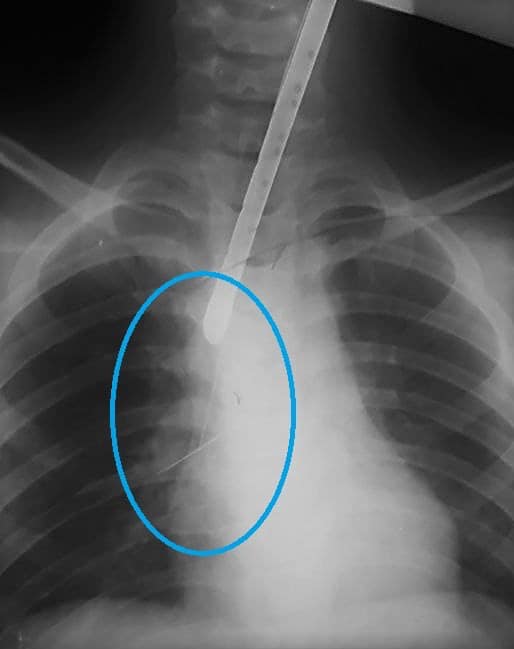

В Днепре в больницу попал ребенок с булавкой в дыхательных путях. В частности, шпилька успела подколоться к трахее, что затруднило ее извлечение.

Так, ребенок проглотил булавку, и во время диагностического эндоскопического исследования оказалось, что она подкололась к трахее.

В частности, доставали посторонний предмет целая бригада медиков. Сначала они пытались ее достать с помощью "петли", но шпилька начала "мигрировать" вниз дыхательными путями. Там до правого бронха она підкололася к сегментарной бронхи и через неосторожное движение могло стать причиной осложнений.

По словам медиков, они просчитали разные варианты развития событий и приняли крайне нестандартное решение, а именно ввести через жесткий бронхоскоп гибкий бронхоскоп.

Медики без операции достали из бронхов ребенка булавку (facebook.com/odkl.org)

Поэтому после некоторых осторожных и медленных манипуляций им удалось удалить злосчастную шпильку из дыхательных путей маленького пациента и почти не травмируя слизистую ни бронха, ни трахеи.